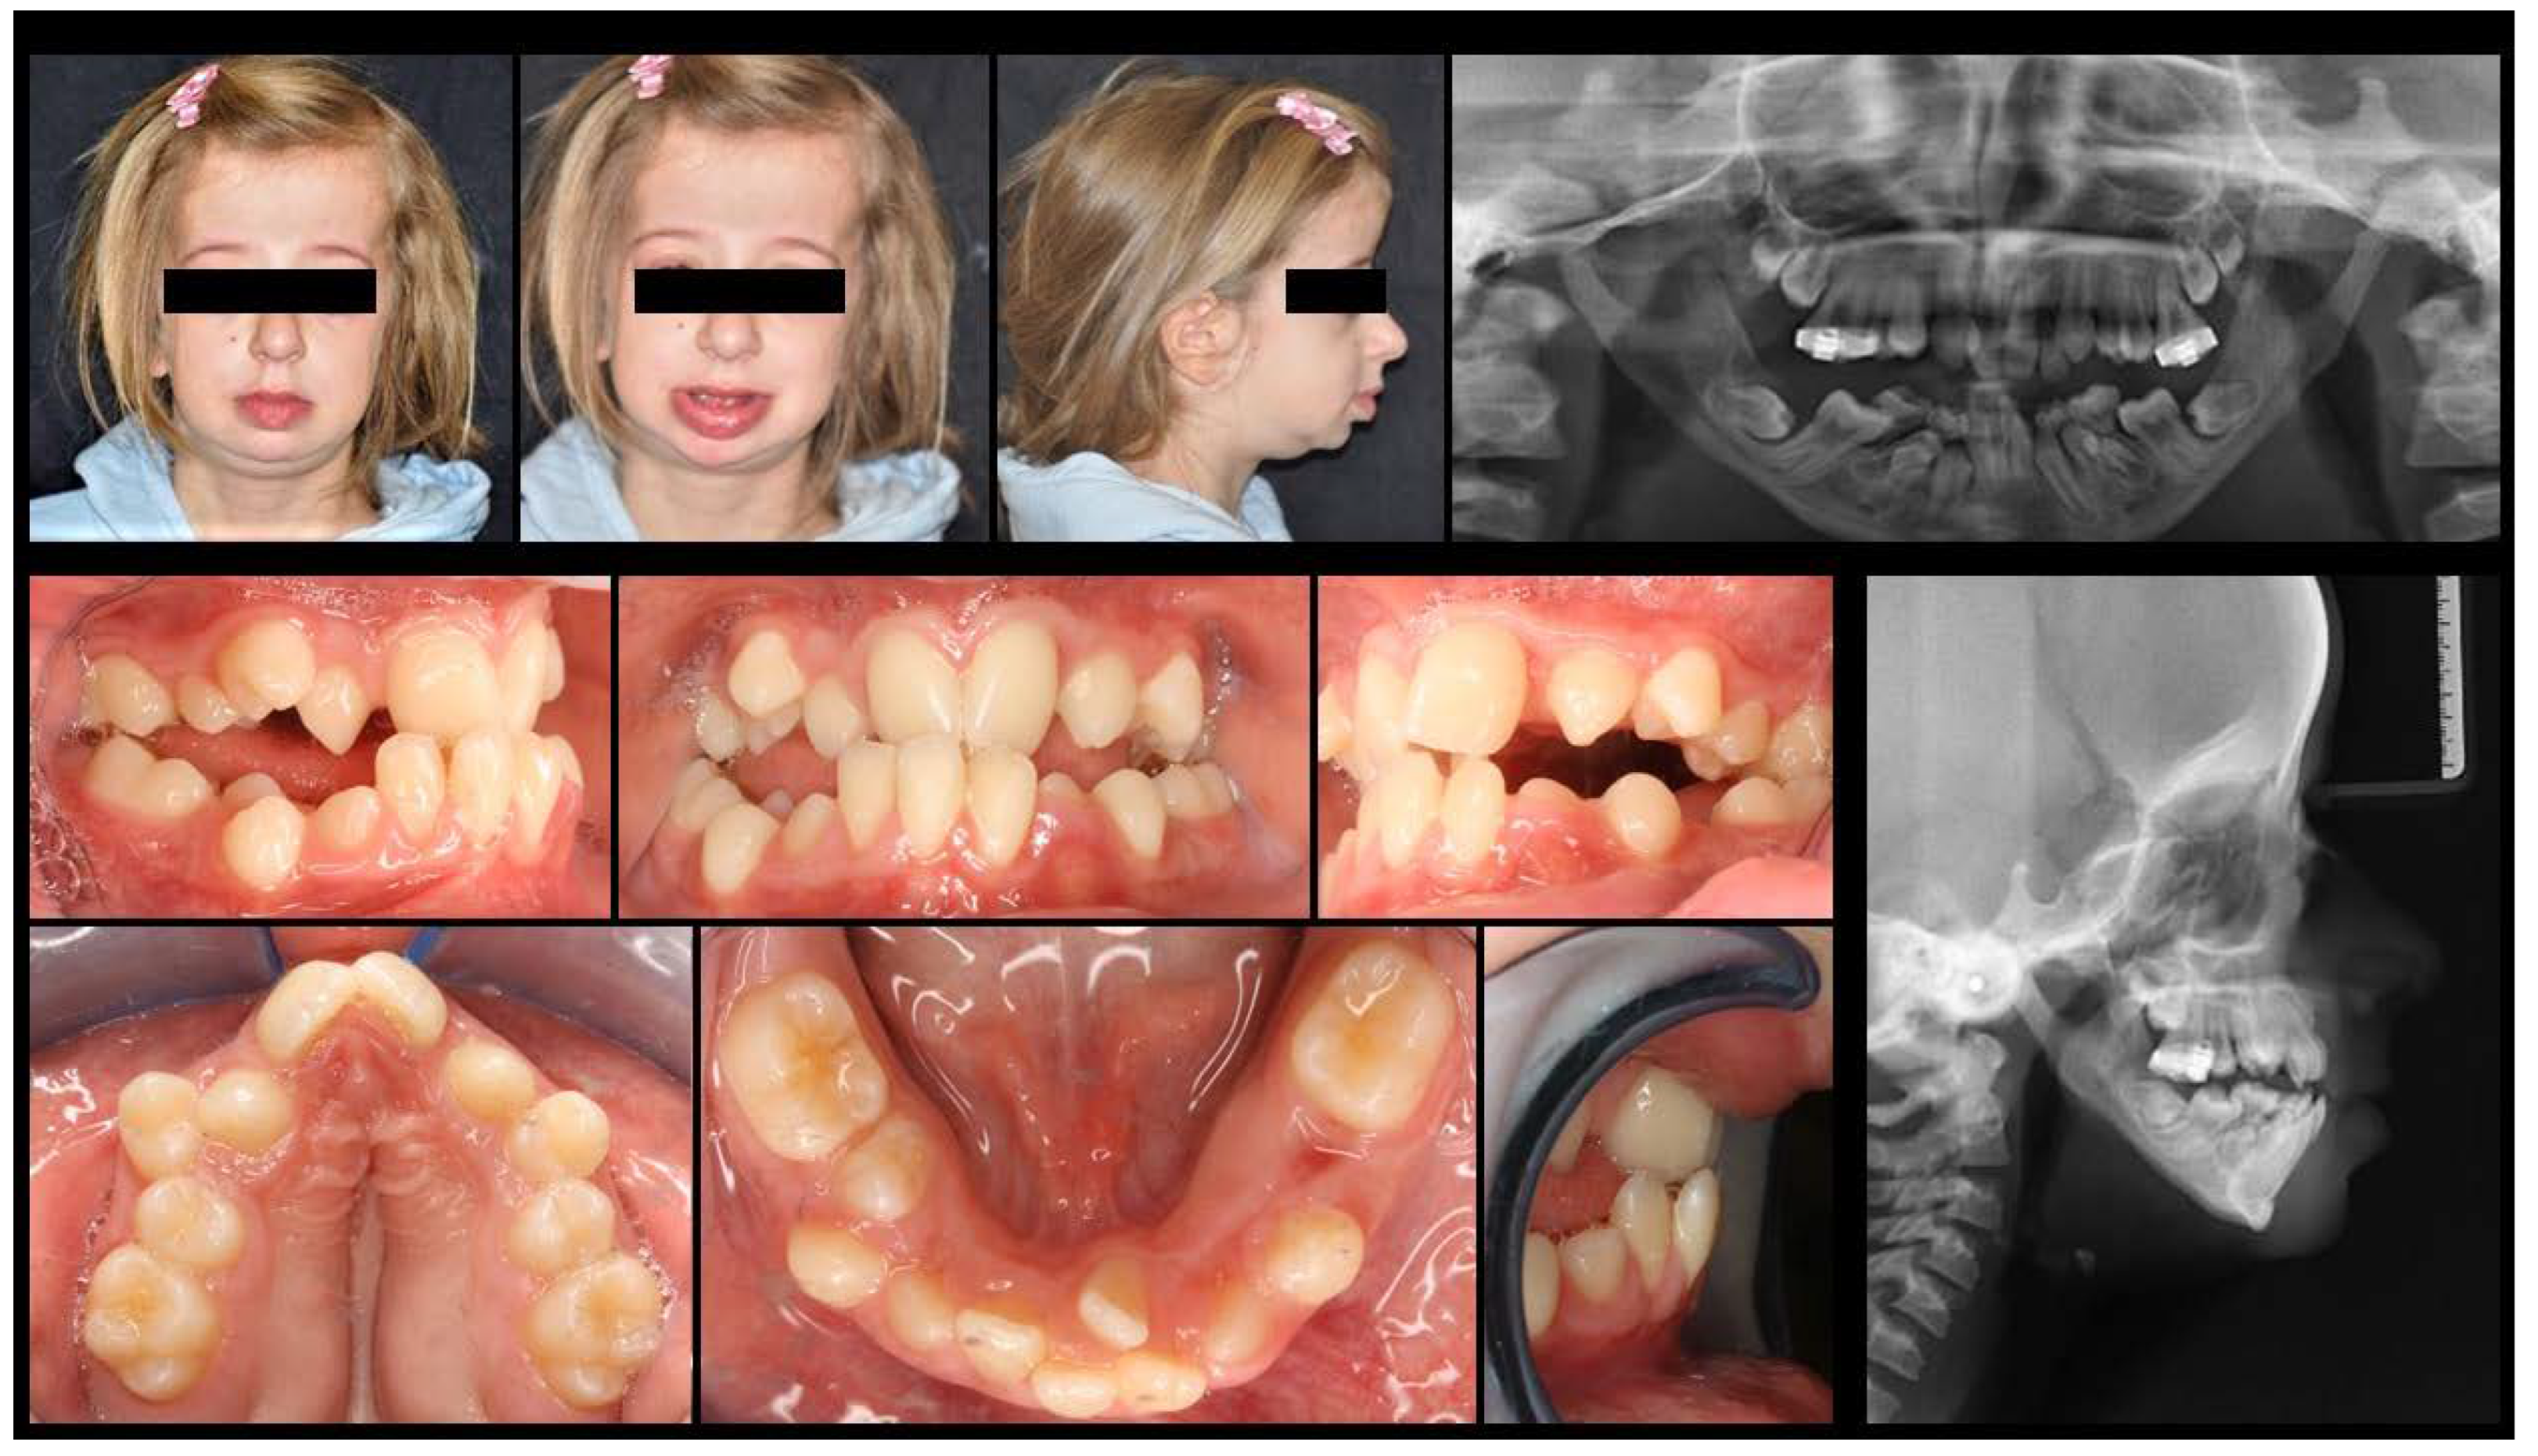

3.1. Orthodontic Results

3.2. Cephalometric Evaluations

3.3. Quantitative Point-Based Assessment of Airway